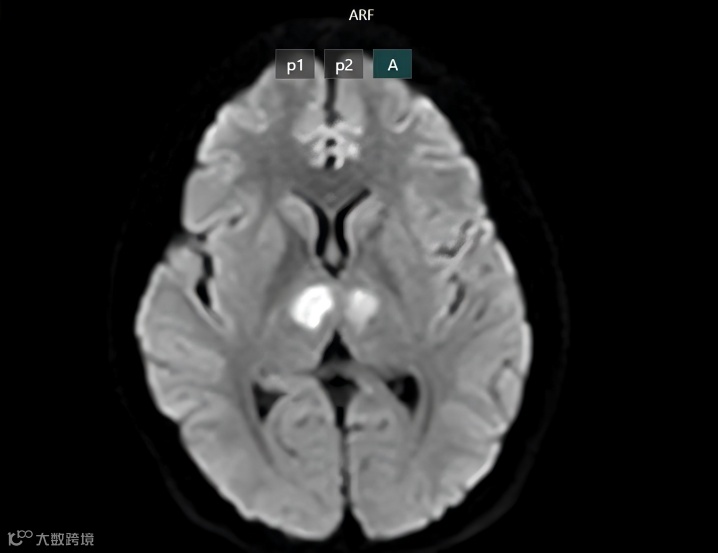

当这位年轻女孩被送入医院后,扫描结果显示她的丘脑两侧均受到了严重损伤。

X光片显示患者的大脑双侧丘脑受损。图片来源:白梅医院

这不是普通的副作用,而是足以改变一个人一生的伤害。